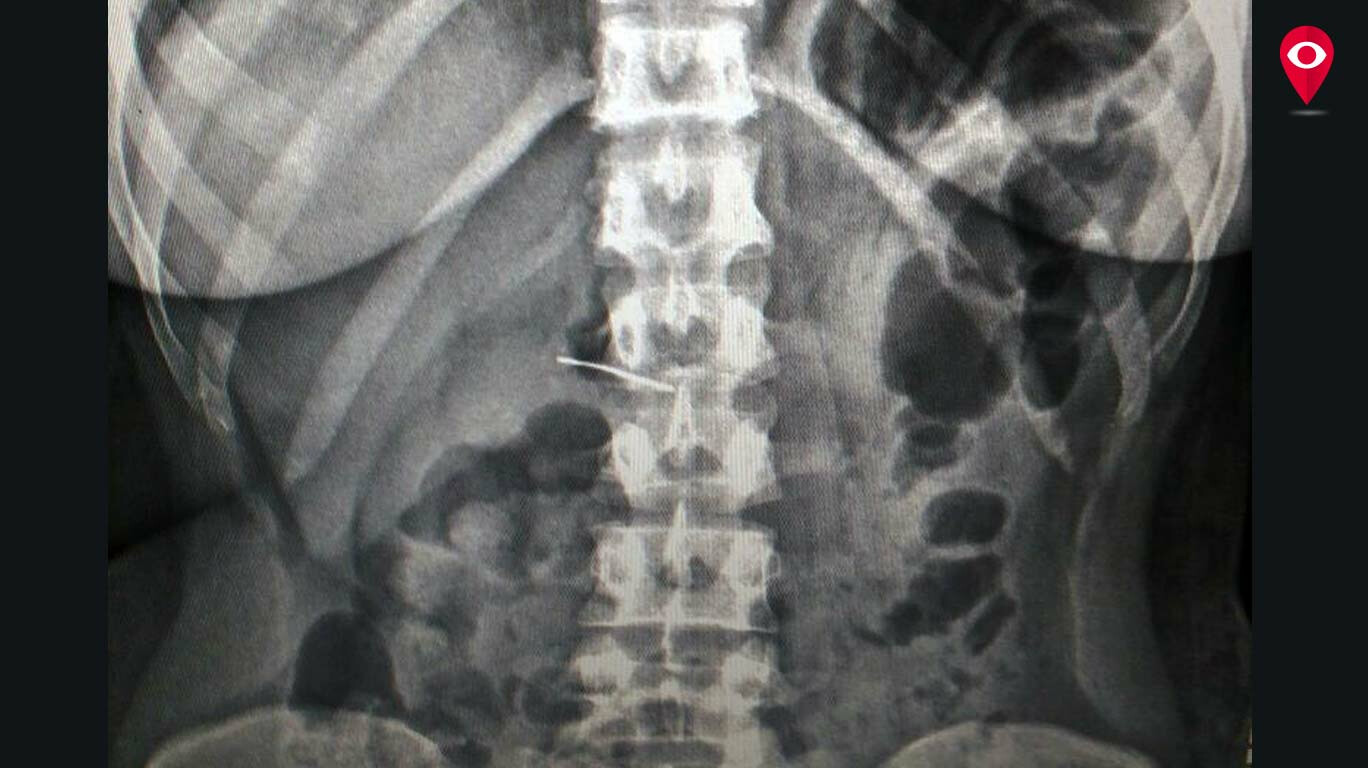

Woman swallows needle while sewing

From www.mumbailive.com

Woman swallows needle while sewing What To Do If You Swallow A Sewing Needle if you or someone you know has swallowed a sewing needle, it’s natural to feel a surge of panic. A healthcare professional will be able to assess the situation and determine the best course of action. The needle can be swallowed or worse get stuck in the back of throat or aspirate into the lungs. The first thing you. What To Do If You Swallow A Sewing Needle.